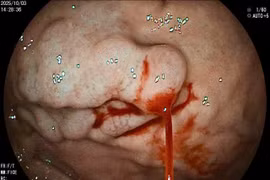

Đau bụng, đầy hơi nhập viện, người đàn ông mới biết bị xuất huyết tiêu hóa

Chủ quan với các triệu chứng như đau bụng, đi ngoài phân đen dễ dẫn đến biến chứng nguy hiểm. Khuyến cáo cần khám sớm khi có dấu hiệu bất thường.